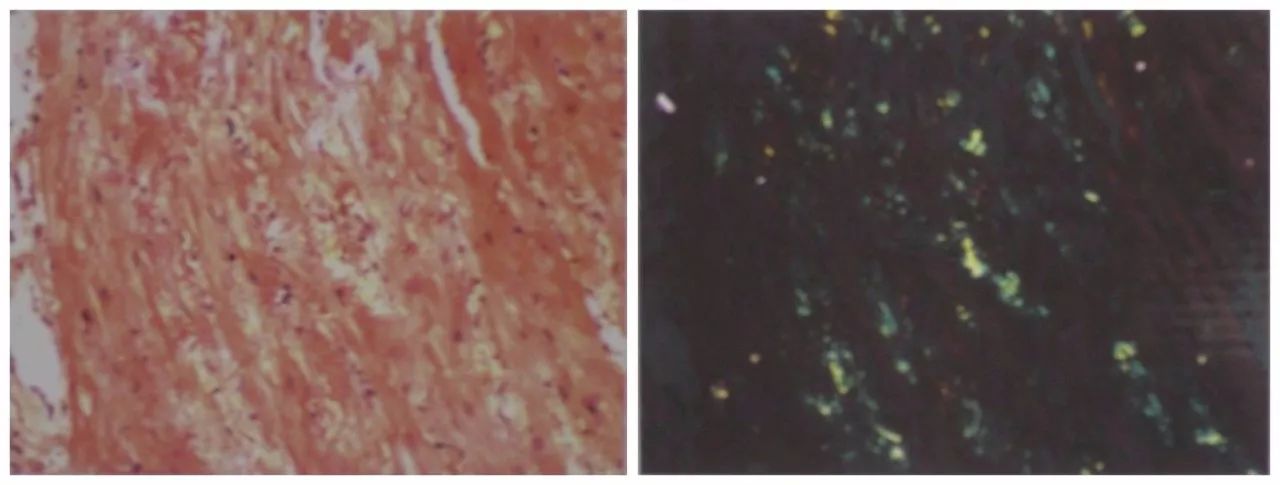

病理:(心内膜心肌活检,腹壁脂肪,齿龈,直肠,肾,骨髓)刚果红染色阳性,

心内膜心肌活检

图左:刚果红染色;图右:偏光显微镜下绿色双折光